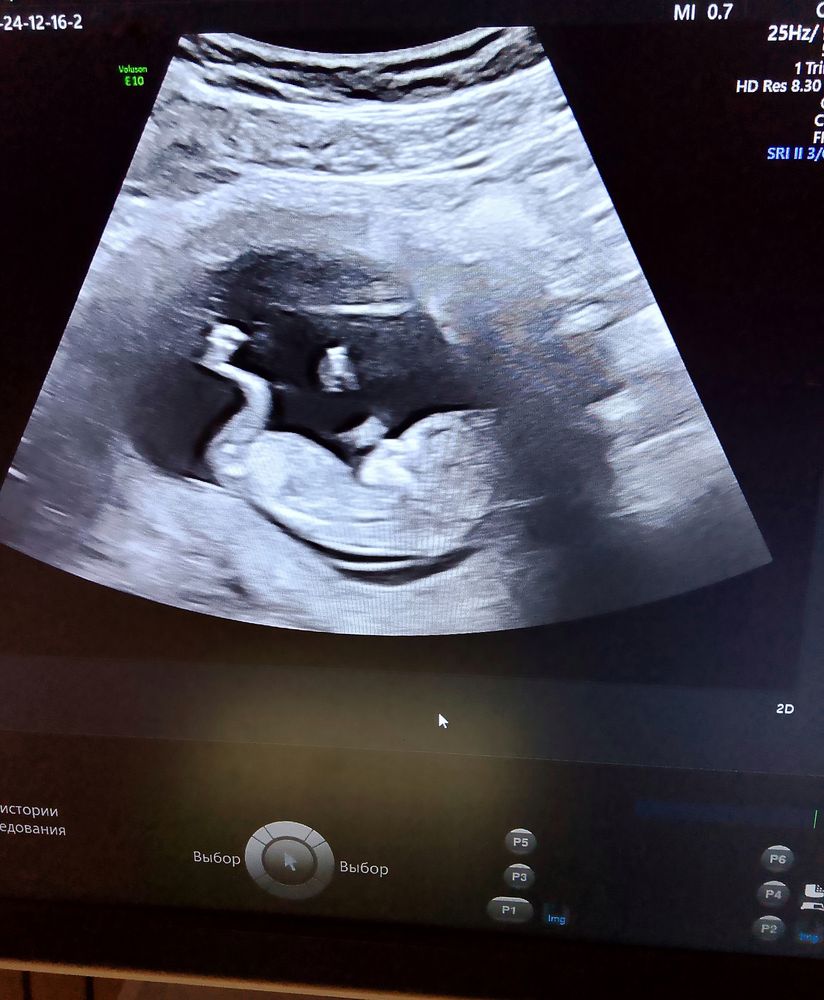

Подскажите, у кого-нибудь определяли пол в 12 недель, хотя бы предположительно, или может кто-то разбирается в этом? Врач на узи сказала, что пол видно будет только с 16 недели. И можно ли что-то понять по снимкам узи? Читала здесь, что у кого-то пол видно было уже в 12-13 недель и не ошиблись)

Обычно видно в 12-13 половой бугорок. Но у вас для этого снимки неудачные, ножкой закрыл малыш.

У вас неудачные снимки. Определить можно с 12 недель ,уже любой нормальный врач может сказать с вероятность 95%

мне с дочкой в 12 недель сказали. по наклону. но у вас не очень хорошо видно

В 12 недель с дочкой определили. Девочки правы, снимки у вас неудачные, бугорка не видно.